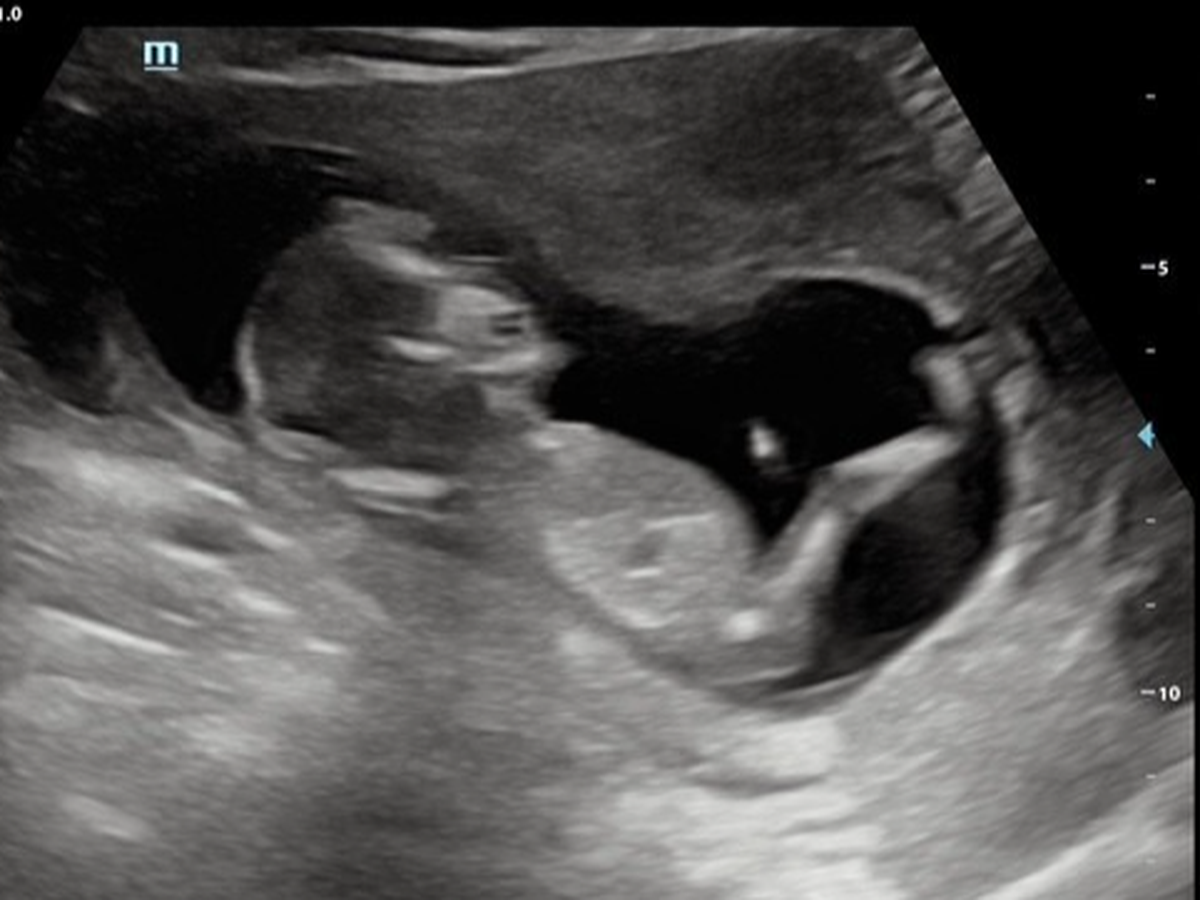

Since they said 'I do' in October 2024, Lys & Justice have been dreaming of the day they would welcome their first child. That dream became a reality when they found out they were expecting a baby boy, whom they’ve named Atlas. At 19 weeks gestation, Atlas is already living up to his name, showing incredible strength as he faces a significant medical journey. Recently, he was diagnosed with a lower urinary tract obstruction that is affecting his amniotic fluid levels and the development of his kidneys and lungs. While we have seen God move already, clearing the path of other complications like placenta previa, Atlas now needs a miracle through fetal intervention. We have been referred to the specialist team at Texas Children’s Hospital in Austin for life-saving surgery. As a young couple starting out, the financial weight of these procedures is overwhelming. With medical costs estimated at $60,000, we are reaching out to our 'village' to help give Atlas the best possible chance at life.